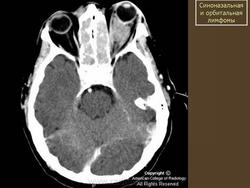

Диагноз злокачественной лимфомы орбиты труден. Из инструментальных методов исследования более информативны ультразвуковое сканирование, компьютерная томография (рис. 20.24, в) и тонкоигольная аспирационная биопсия с цитологическим исследованием. Необходимо обследование у гематолога для исключения системного поражения. Наружное облучение орбиты — практически безальтернативный высокоэффективный метод лечения. Полихимиотерапию подключают при системном поражении. Эффект лечения проявляется в регрессии симптомов патологического процеса в орбите и восстановлении утраченного зрения. Прогноз при первичной злокачественной лимфоме для жизни и зрения благоприятный (83 % больных переживают 5-летний период). Прогноз для жизни резко ухудшается при диссеминированных формах, но частота поражения орбиты при последних составляет чуть более 5 %.